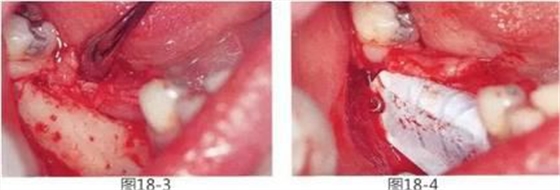

圖18-3 將粘膜剝離,露出牙槽嵴的狀態(tài)??梢钥吹窖啦坩辗浅1 榱舜龠M(jìn)牙槽嵴出血,在皮質(zhì)骨上進(jìn)行穿孔。

圖18-4 進(jìn)行骨移植后,使用釘子將Gore-Tex鈦強(qiáng)化膜固定。